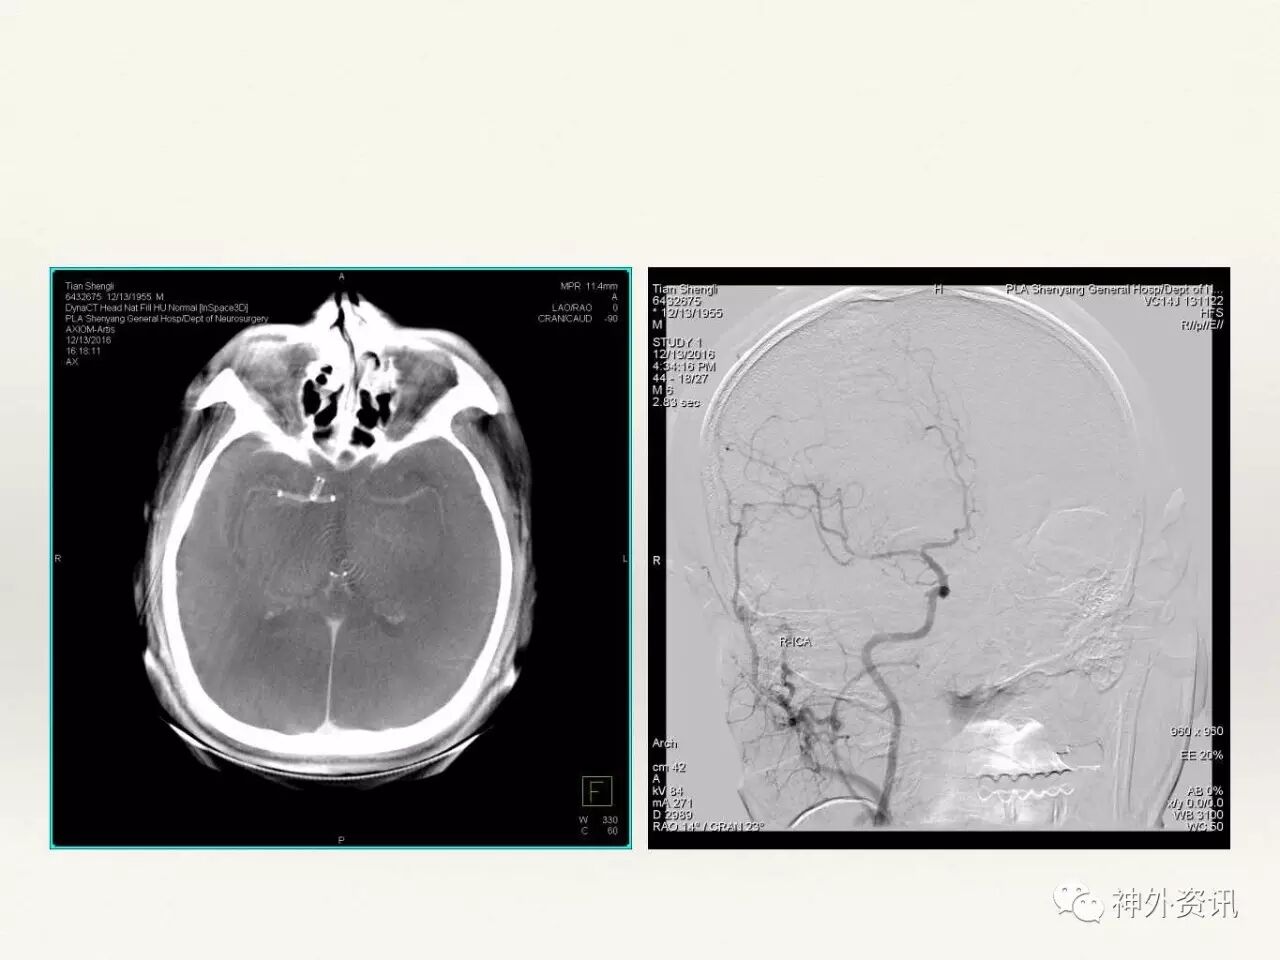

在东北地区率先开展了颈内动脉、大脑中动脉及基底动脉闭塞血管内再通、颅内动脉栓塞急性期取栓、血流导向装置治疗大型宽颈动脉瘤等,对颅内动脉瘤、动静脉畸形、颈动脉及颅内动脉狭窄、颈内动脉海绵窦瘘、硬脑膜动静脉瘘等外科治疗具有较深的造诣。完成脑血管造影8600余例,各类脑血管病介入手术共4500余例,动脉瘤、动静脉畸形、脑肿瘤、脑出血及脑外伤等外科手术1500余例。